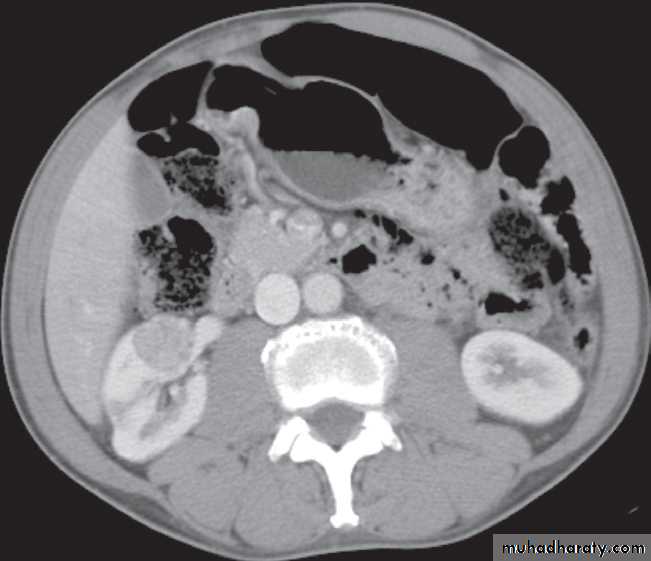

-A typical simple renal cyst is a spherical mass with an imperceptible wall . The interior of the cyst is homogeneous with attenuation values similar to water.

Renal masses are usually first detected at ultrasound examination.Ultrasound can establish whether a mass is a simple cyst and can, therefore, be ignored, or whether the lesion is solid and, therefore, is likely to be a renal carcinoma.( further evaluation with CT is indicated ) .

-A mass with mixed cystic and solid features falls into the indeterminate category and could be a renal tumour, a renal abscess, or possibly a complex benign cyst or other benign condition ( also further evalution with CT scan is indicated )